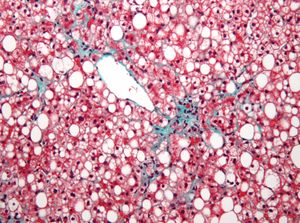

- '''지방간 질환(간 지방증)''': 간세포에 트리글리세리드 지방이 축적되는 가역적인 상태이다.[7]

- 지방간 질환 (간 지방증)은 간세포에 트리글리세리드 지방의 큰 공포가 축적되는 가역적인 상태이다.[7] 비알코올성 지방간 질환은 비만 및 대사 증후군과 관련된 일련의 질병이다.[8]